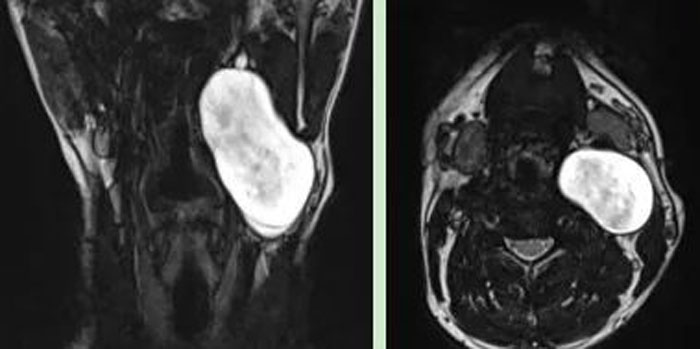

患者,男,26歲,2年前發(fā)現(xiàn)頸部左側(cè)腫物,逐漸增大,來我院就診。彩超示:左側(cè)頸部探及約5.0×4.3cm低回聲團(tuán)塊;頸部MRI示:左側(cè)頸部囊性占位,考慮良性病灶,大小約3.5×5.1×7.2cm。

患者年紀(jì)輕,病情復(fù)雜,經(jīng)充分準(zhǔn)備后,在牛善利主任指導(dǎo)下,牛傳貴副主任醫(yī)師、步明強(qiáng)副主任在全麻下實施頸部腫物切除術(shù)。術(shù)中見腫物位于頸動脈鞘內(nèi),將頸內(nèi)靜脈及迷走神經(jīng)擠向外側(cè),將頸內(nèi)、外動脈擠向內(nèi)側(cè),腫物下緣至環(huán)狀軟骨水平,上緣至二腹肌后腹深面向上近顱底處。此次手術(shù)難度大,手術(shù)操作復(fù)雜,手術(shù)風(fēng)險大,技術(shù)要求高,在手術(shù)室李蘊(yùn)護(hù)士長、張建永護(hù)士長、楊凌主管護(hù)師及麻醉科鄧燕副主任醫(yī)師密切合作下,手術(shù)順利完成。病理參考免疫組化報告神經(jīng)纖維瘤。術(shù)后患者恢復(fù)良好,已出院。(耳鼻咽喉科)